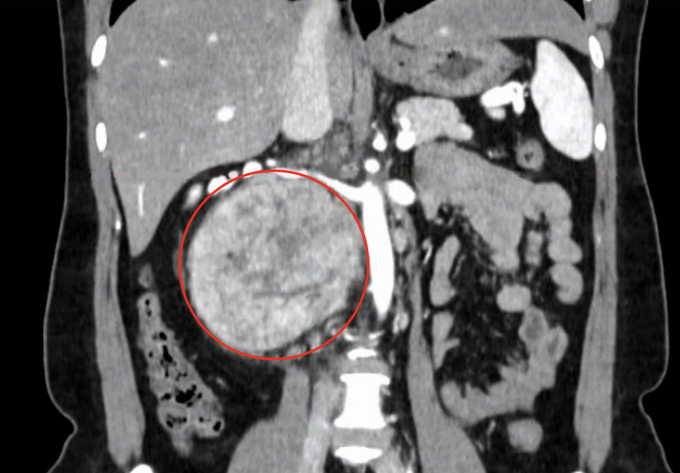

Chị Ngà từng được bác sĩ chẩn đoán bị thoát vị đĩa đệm song điều trị bằng thuốc không bớt đau. Chụp CT tại Bệnh viện Đa khoa Tâm Anh TP HCM cho thấy khối u 12 cm ở vùng sau phúc mạc - khoang ổ bụng và cột sống lưng. Loại u này thường phát sinh từ mô, thần kinh, tế bào mầm hoặc các nang sau phúc mạc.

Khối u lớn sau phúc mạc của chị Ngà. Ảnh: Bệnh viện Đa khoa Tâm Anh